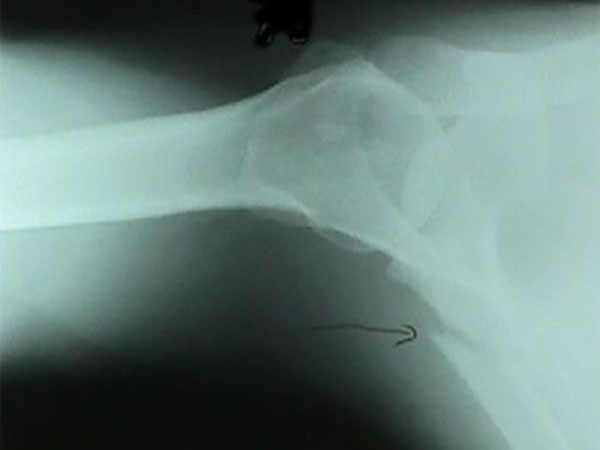

肩甲骨骨折は、レントゲン画像では読み取りにくいことがあります。肋骨が画像読影の邪魔をすることがあるためです。

もっとも、次のようなCT画像だと容易に判断できます。